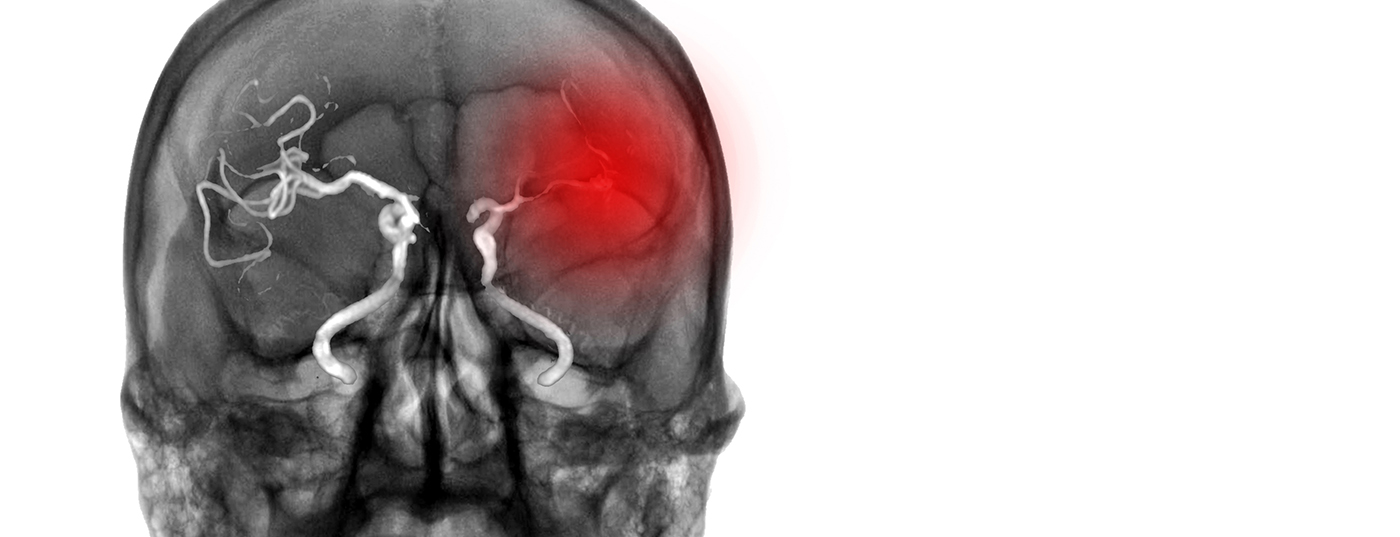

In der TASTE-A-Studie zeigte Tenecteplase bei Schlaganfallpatienten im mobilen Stroke-Unit-Einsatz eine überlegene Wirkung gegenüber Alteplase. Die Substanz könnte dank einfacher Bolusgabe und höherer Fibrinspezifität helfen, die Zeit bis zur Reperfusion entscheidend zu verkürzen – ohne erhöhtes Blutungsrisiko.